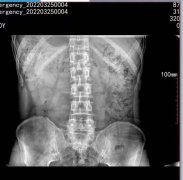

5kw移动式x光机能拍腰椎吗?

5kw移动式x光机能拍腰椎吗?可以的,我们的小伙伴都试验过,可以拍摄腰椎正位和侧位,正位效果比侧位效果要好。以下是拍摄腰椎正位的效果图:简单给大家介绍下我司的便携机产...更多